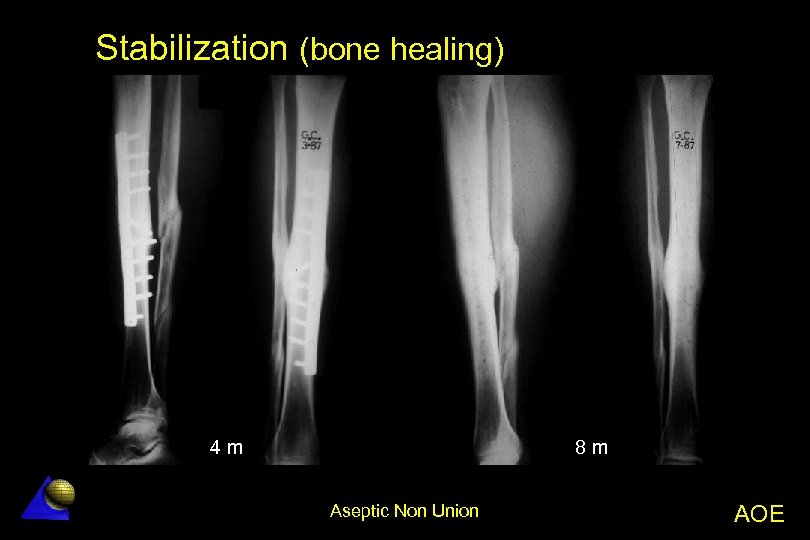

Stabilization (bone healing) 8 m 4 m Aseptic Non Union AOE

“Elephant foot” non-union healed after plating stabilization Aseptic Non Union AOE